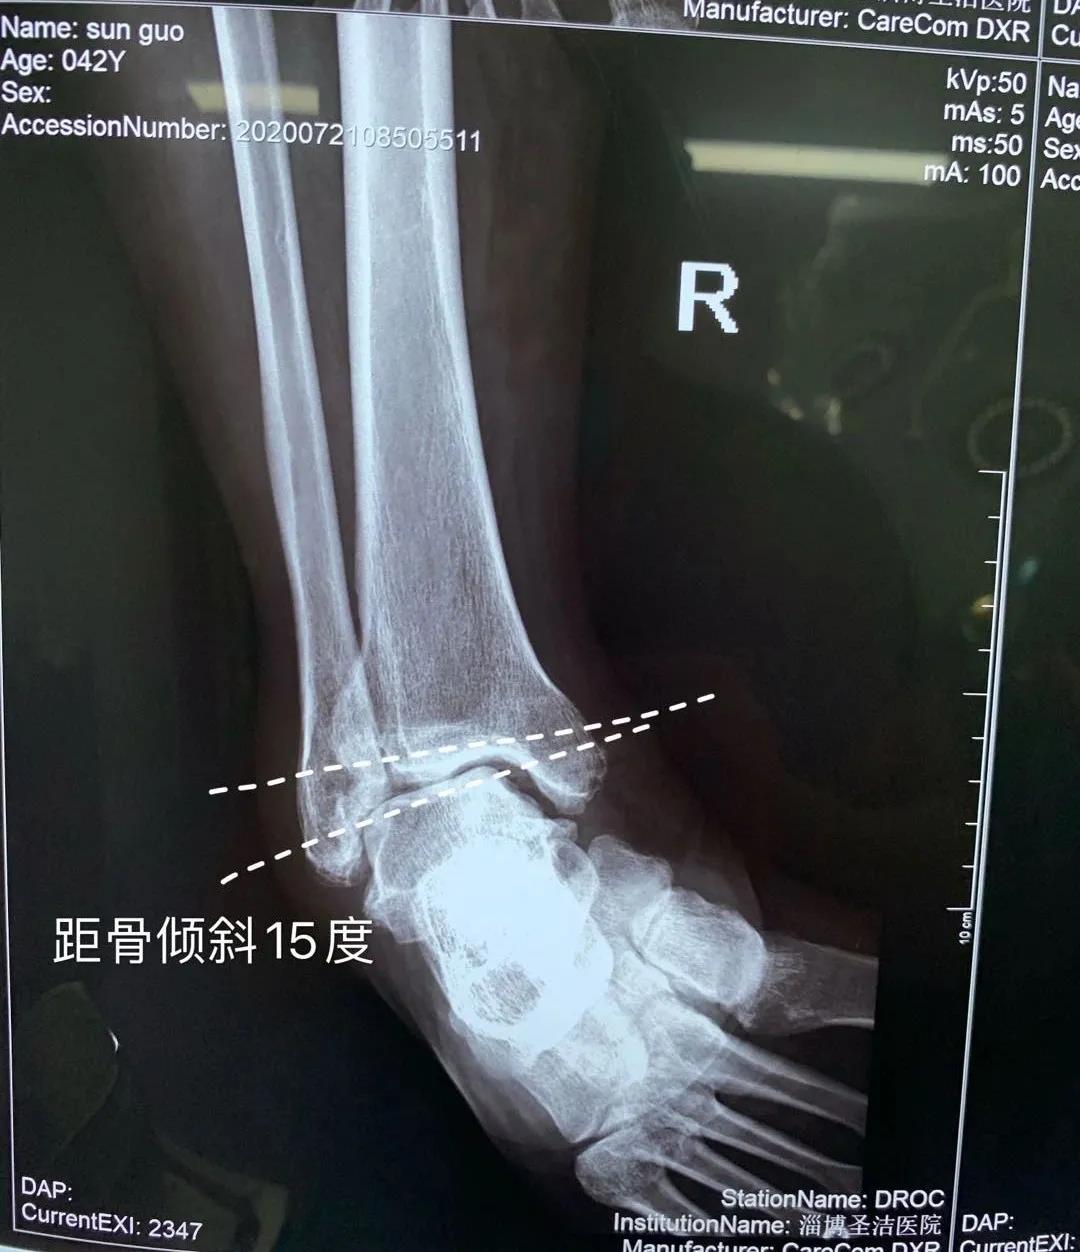

近日,醫(yī)院骨二科成功治療一位關(guān)節(jié)反復(fù)疼痛病人。患者李某,男,42歲,踝關(guān)節(jié)外傷導(dǎo)致外側(cè)韌帶損傷踝關(guān)節(jié)不穩(wěn),長(zhǎng)期沒有及時(shí)治療導(dǎo)致踝關(guān)節(jié)骨關(guān)節(jié)炎的發(fā)生。患者踝關(guān)節(jié)疼痛不能長(zhǎng)距離行走這是術(shù)前應(yīng)力位片提示踝關(guān)節(jié)距骨傾斜,踝關(guān)節(jié)踝前撞擊綜合癥,給予踝關(guān)節(jié)鏡下關(guān)節(jié)腔清理,骨贅切除,并給予外側(cè)韌帶重建恢復(fù)關(guān)節(jié)穩(wěn)定性。目前,患者手術(shù)后的踝關(guān)節(jié)穩(wěn)定,功能恢復(fù)良好,即將康復(fù)出院。